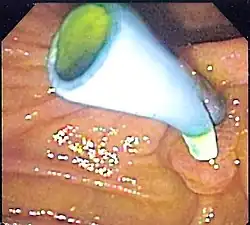

A colon stent is typically made of flexible metal mesh that can expand and hold open the blocked area, allowing for the passage of stool. Colon stents are used primarily as a palliative treatment for patients with advanced colorectal cancer who are not candidates for surgery. They help relieve symptoms such as abdominal pain, constipation, and bowel obstruction caused by tumors or strictures in the colon.

The placement of a colon stent involves endoscopic techniques similar to esophageal stenting. A thin tube called an endoscope is inserted into the rectum and guided through the colon to locate the blockage. Using fluoroscopy or endoscopic guidance, a guidewire is passed through the narrowed area and then removed after positioning it properly. The stent is then delivered over the guidewire and expanded to keep open the obstructed section of the colon. Complications associated with colon stents include perforation of the intestinal wall, migration or dislodgment of the stent, bleeding, infection at insertion site, or tissue overgrowth around it.[10]

Colon stenting provides several benefits including prompt relief from bowel obstruction symptoms without invasive surgery in many cases. It allows for faster recovery time compared to surgical interventions while providing palliative care for patients with advanced colorectal cancer by improving quality of life and enabling better nutritional intake. However, there are potential risks associated with complications such as migration or obstruction that may require additional procedures or interventions to address these issues effectively.[11]